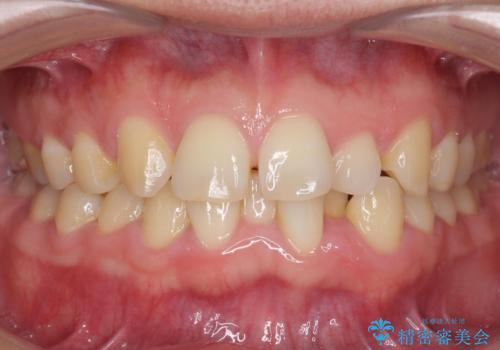

すきっ歯 歯を抜かない矯正治療

- 前歯のすき間を主訴に来院。

非抜歯マルチブラケット治療によりすき間を閉じることとした。

前歯部の被蓋が浅く、開咬傾向であった。

舌癖が認められたため、筋機能訓練も併せて行った。

スペースを閉鎖するにあたり前歯部を後方移動したため、口元もすっきりしました。